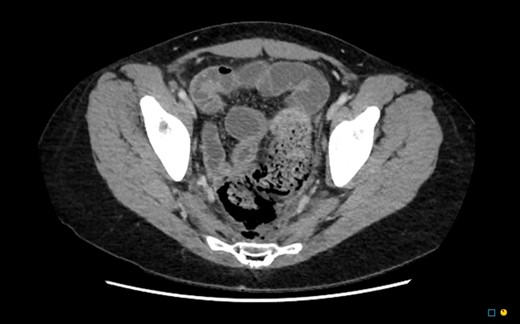

In the regional hospital, the patient had progressive peritonitis and vomiting. He was tachycardic and febrile (Temp 38.5°C). His initial work up demonstrated urea 11.9 mmol/l, creatinine 121 umol/l, C-reactive protein 201 mg/l, white cell count 30.7 × 109/l and haemoglobin 112 g/l. An urgent CT abdomen and pelvis demonstrated a large amount of free gas in the perirectal space consistent with a rectal perforation (Figs 1–3). The rectum itself was thick-walled and oedematous, as well as the sigmoid colon. He was transferred to the referral Tertiary hospital where an urgent laparotomy was performed.

CT sagittal. Large amount of perirectal free gas consistent with rectal perforation. The rectum is thick-walled and oedematous suggestive of ischaemia.